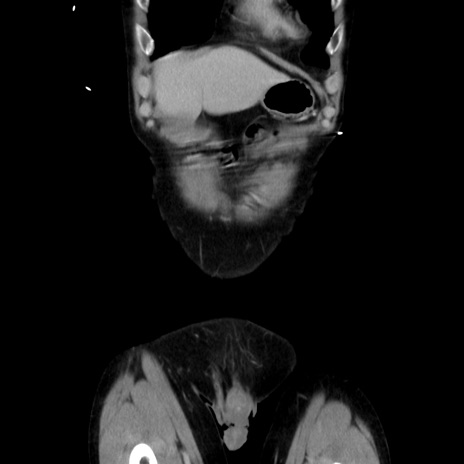

症例37(冠状断像)

【症例】40歳代 男性

【主訴】腹痛

【現病歴】4時間ほど前に電車に乗車中に臍部上より腹痛出現。徐々に増悪し起立困難となり、救急外来受診。生ものは数日食べていない。今朝お雑煮を食べた。

【既往歴】なし

【身体所見】BT 36.8℃、BP 117/84mmHg、HR 91/min、SpO2 97%、苦悶様、腹部:臍上部広範囲圧痛あり、反跳痛±

【データ】WBC 8100、CRP 0.03